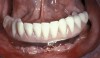

Fig 7. Existing dentition was sound periodontally and reasonably esthetic.

Figure 7

Interceptive implant therapy may then become a consideration earlier in life to create restorations that will not be subject to the latent effect of dental caries as aging continues. An example is shown in Figure 6 and Figure 7; the panoramic film of a 56-year-old man shows several orthognathic and extensive dental procedures historically. All full-coverage restorations had been replaced for a second time, and, again, all evidenced recurrent caries, but the existing dentition was periodontally sound and relatively esthetic.

The choice of removing a caries-challenged but restorable dentition at a younger age is ethically complex. Ultimately, the decision is the patient's alone based on informed consent of all available options. The removal of a potential lifetime of caries activity that is now more predictable than ever may be a viable option for this high-risk segment of a younger patient base.